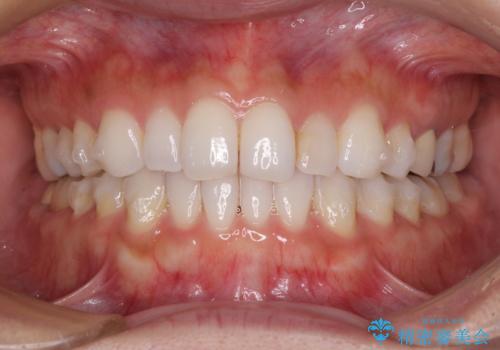

軽度の叢生をインビザライン・ライトで解消

- 前歯が気になるとのことで来院された患者様です。

歯列不正は軽微であったため、インビザライン・ライトにより、費用を抑えて矯正治療を行うこととしました。

短期間で気になる前歯の歯列を改善することができました。